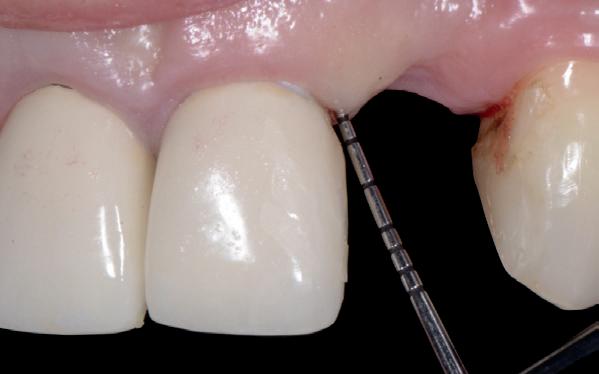

Mevrouw werd naar het Dental Design Center verwezen om een complex probleem aan het bovenfront te beoordelen en indien mogelijk te behandelen. Tien jaar geleden zijn er om esthetische redenen op de 12, 11, 21 en 22 kronen geplaatst. Helaas bleek achteraf een wortelkanaalbehandeling van de 22 noodzakelijk. Na een aantal jaar ontstond er weer een infectie apicaal aan de 22 en werd er een apex uitgevoerd. Helaas had deze behandeling niet het beoogde resultaat. Twee weken voordat ze bij mij op consult kwam, is het element geëxtraheerd en is er een partiële plaat geplaatst als tijdelijke oplossing (foto 1-3).

Na de IPP (esthetisch/functionele) analyse blijkt dat de gezichts- en faciale mediaan niet geheel overeenkomen en dat de gingiva lijnen van het bovenfront niet helemaal parallel lopen met de interpupillaire lijn. Na overleg met mevrouw kiest zij ervoor om dit niet orthodontisch te laten corrigeren. Mevrouw

heeft de nadrukkelijke wens om geen brugconstructie te krijgen. Om die reden is een etsbrug of een conventionele brug geen optie. Daarom bestaat het behandelvoorstel uit vier losse kronen waarvan de 22 implantaat gedragen zal zijn. Een gedetailleerd onderzoek van de regio 22 is noodzakelijk (foto 4-6).

Uit het röntgenonderzoek blijkt dat op de locatie van de 22 veel bot verloren is gegaan en dat er niet direct een implantaat geplaatst kan worden. Om die reden is een botaugmentatie geïndiceerd. Wel zijn distaal van de 21 en mesiaal van de 23 de botpieken aanwezig die de papillen ondersteunen. Naast te weinig bot, is op de locatie 22 in bucco-linguale richting ook te weinig volume gingiva aanwezig. Daarom zal er tevens een soft tissue graft aangebracht worden. Tijdens deze behandeling wordt ook de recessie op de 23 zoveel mogelijk bedekt (foto 7 en 8).

Na vier maanden wordt er een CBCT gemaakt om het botvolume te kunnen beoordelen en een digitale planning te kunnen maken voor het plaatsen van het implantaat. Tevens wordt de stabiliteit van de botpieken op het buurelementen bekeken (foto 15 en 16).

De flap en graft worden met poly-propelene 6.0 hechtingen gefixeerd. De tijdelijke reconstructie wordt herplaatst (foto 17-20).

Na 4-6 weken kan het aangebrachte healing abutment worden vervangen door een tijdelijk abutment. Deze wordt aan de kunststof reconstructie verbonden om zo de gingiva ter plaatse van de 22 te vormen. Zo lijkt het of er geen implantaat maar nog steeds een wortel aanwezig is, wat het esthetisch eindresultaat ten goede zal komen (foto 21-23). Vanaf 4-6 maanden ziet het weefsel er gezond uit. Nu kan met de uiteindelijke restauratiefase worden gestart (foto 24 en 25).